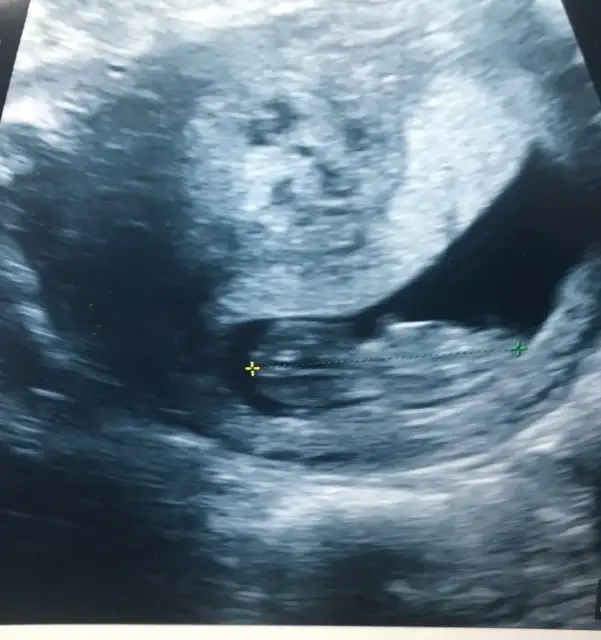

Kafasi kare gibi sanki erkek ama goruntuyu yakinlastirmamis doktor emin olamadim

Ben erkek diyorum cunku cenesi belirgin degil ve alni duz

Kiz gibi Geldi banaBenim bebegin de cinsiyeti hakkinda yorum yapabilir misiniz?